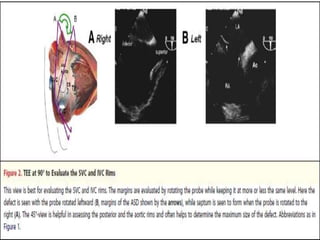

FOR A COMPREHENSIVE EVALUATION OF THE ASD, TEE IS PERFORMED

IN 3 DIFFERENT PLANES: TRANSVERSE (0°), LONGITUDINAL (90°), AND AT

45°.